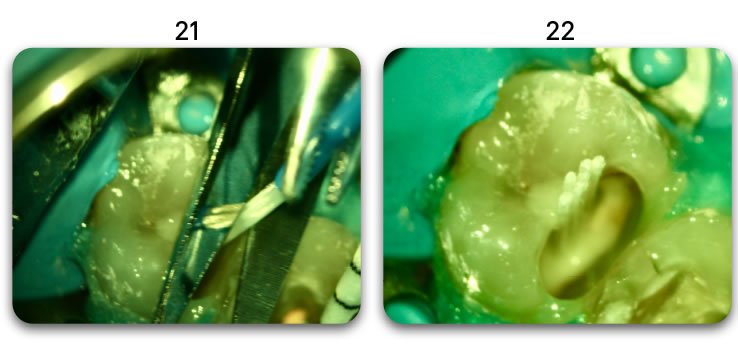

Gabarit pour radiographie

(Avec 4 micro-tenons Biolight® DRILL-FREE)

• Avec Biolight® ST – 1.0mm (1 seul tenon)

• Avec Biolight® DRILL-FREE – 1.0mm (4 micro-tenons)

Les Reconstitutions Corono Radiculaires renforcées avec des multi-tenons fibrés Biolight® DRILL-FREE (4 micro-tenons) résistent à des forces en traction à rupture supérieures de 41% par rapport à celles renforcées avec des tenons fibro architecturés préfabriqués centro-canalaires Biolight® ST de ø équivalent 1,0mm.

(Avec 12 micro-tenons Biolight® DRILL-FREE)

• Avec Biolight® ST – 1.5mm (1 seul tenon)

• Avec Biolight® DRILL-FREE – 1.55mm (12 micro-tenons)

Les Reconstitutions Corono Radiculaires renforcées avec des multi-tenons fibrés Biolight® DRILL-FREE (12 micro-tenons) résistent à des forces en traction à rupture supérieures de 120% par rapport à celles renforcées avec des tenons fibro architecturés préfabriqués centro-canalaires Biolight® ST de ø équivalent 1,5mm.